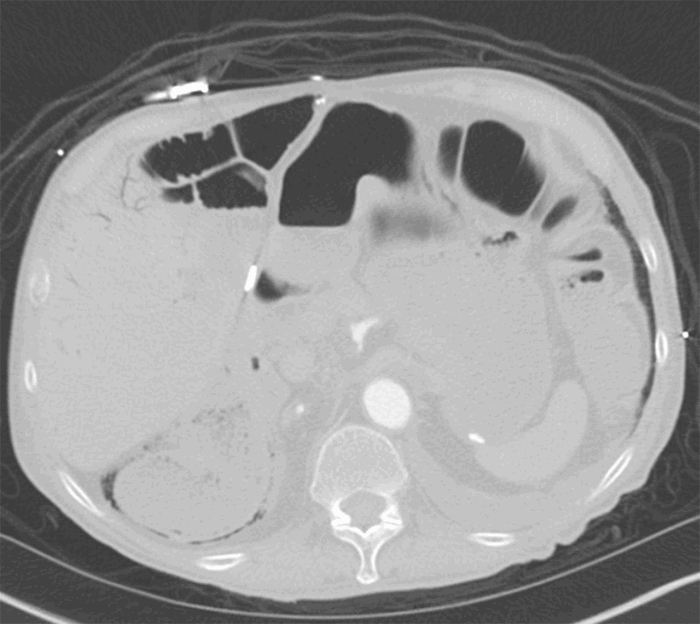

CT angiogram was pursued and demonstrated worsening pneumatosis of the right colon, superior mesenteric artery with small caliber distal branches, and portal venous gas (Figure 1). Arterial lactic acid was elevated to 2.8 mmol/L. At this time, SMA ischemia was suspected, and surgical management was undertaken. The patient received right hemicolectomy, end ileostomy, and mucus fistula. A small colonic perforation was noted intraoperatively.

Figure 1. CT image, axial view. Pneumatosis intestinalis of the ascending colon with suspected free air. Portal venous gas can be seen within the liver.